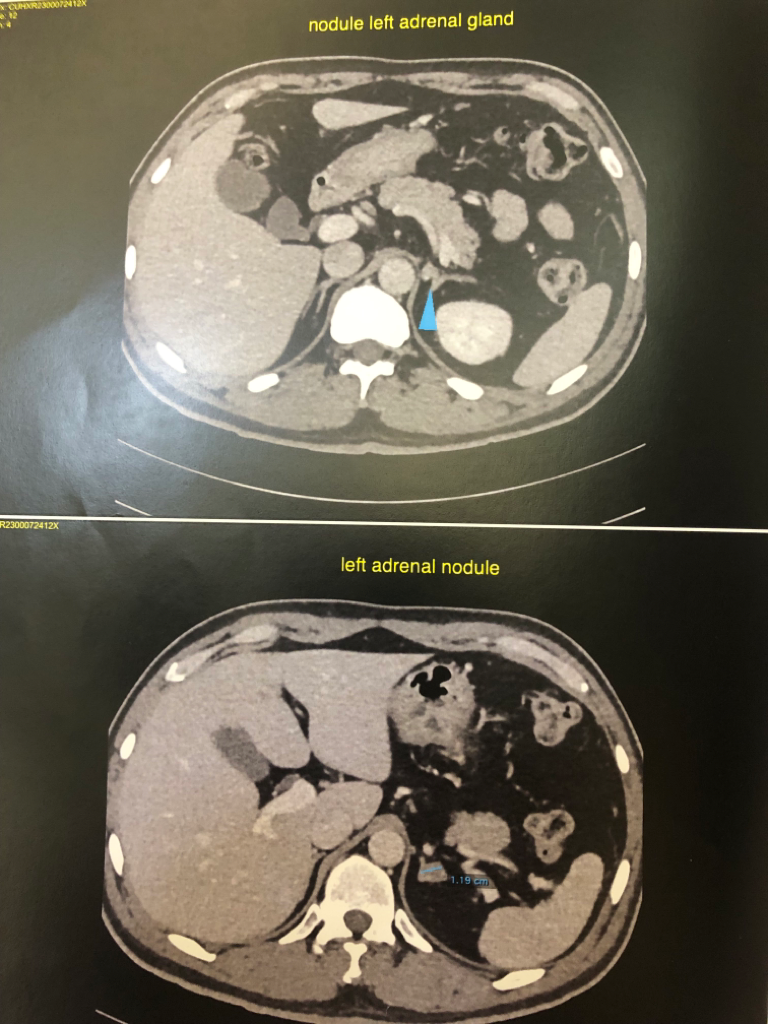

양쪽 부신에 낭종이 있고, 신장에 결석인지 물혹인지가 있고 폐 석회화,경증의 전립선 비대 등등이 있다고 알고 있는데요

• 7번 째 사진

• 8번 째 사진